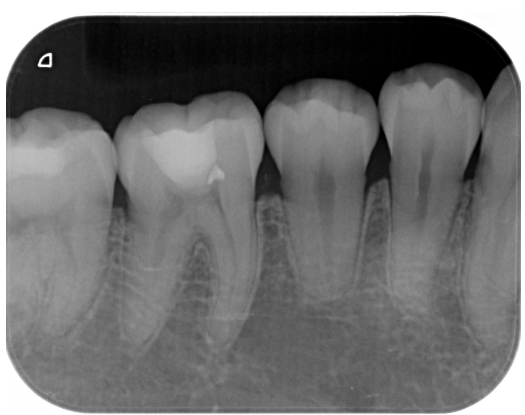

症例3

| 患者様データ | 20代 男性 |

| 来院時の主訴 | 「虫歯の治療をしたい。症状はない。」 |

| 術前検査結果 | 歯髄の生活反応有り、自覚症状無し |

| 医院の診断 | 無症候性可逆性歯髄炎 |

| 通院期間 | 1年間 |

| 来院回数 | 3回 |

| 治療費 | 総額:112,000円(税抜) 【内訳】 歯髄保存療法(MTA使用)40,000円、ダイレクトボンディング治療70,000円、術後経過観察時検査代1,000円×2回分 |

| リスクと副作用 | ①適応症が限られる ②時間が経過してからトラブルが生じることがあるため、長期的(約半年〜4年)な経過観察が必要 |

| ここがこだわりのポイント!☝ | 慢性う蝕の場合、術前症状がなくても、歯髄にまで細菌感染が生じているケースは珍しくありません。患者様は術前に症状の訴えはありませんでしたが、歯の神経にまで細菌感染が生じており、神経の除去を勧めたところ、歯髄保存療法を希望されました。MI治療が可能と判断したので、年齢も若いことから治療後は歯を極力削らない治療で終了しています。 |